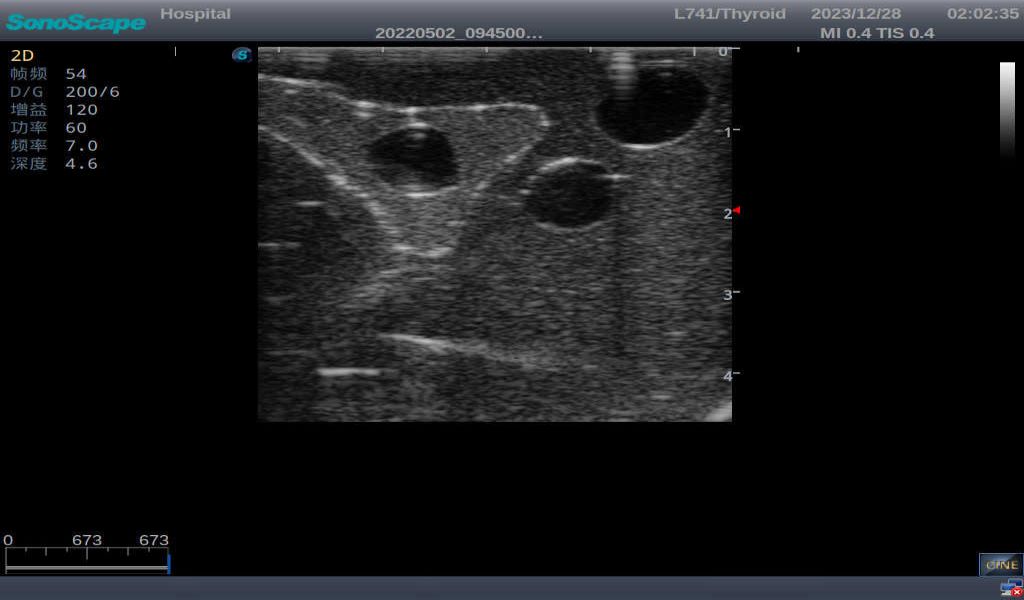

3) It comes with four (4) thyroid modules and can show five (5) ultrasonic images: normal thyroid, thyroid adenoma, thyroid cancer, nodular goiter, thyroid cyst

Normal thyroid with homogeneous parenchymal echo and well-defined capsule

Thyroid cyst, which fluid area, dark and echo-free area can be seen